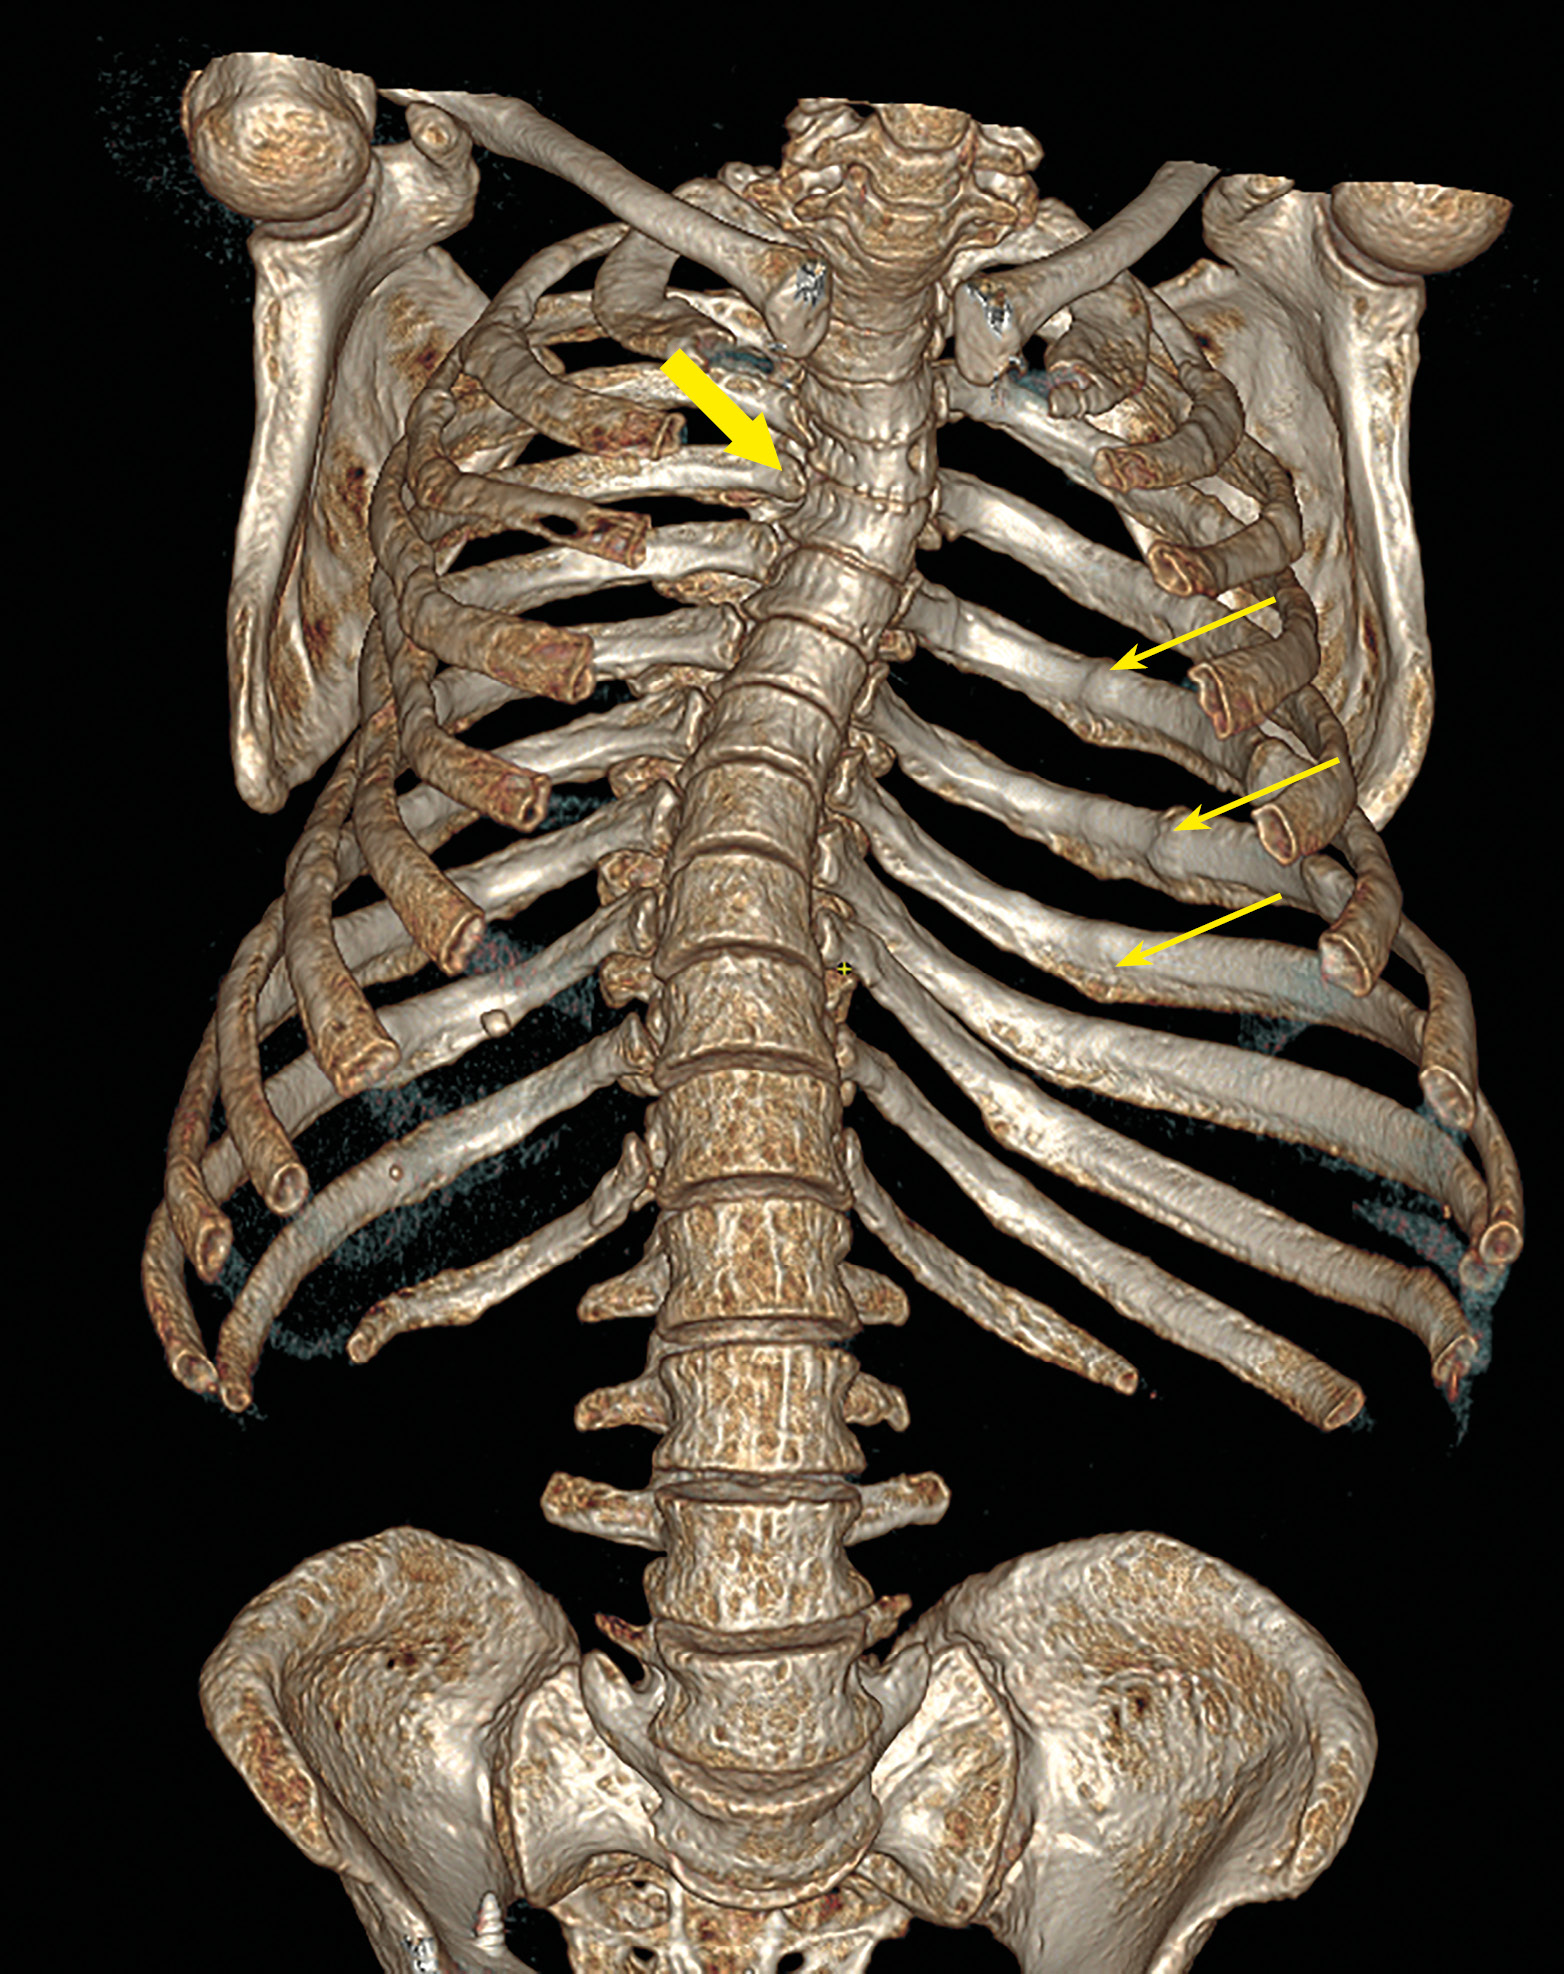

4. Рисунок 4. Пациентка П. КТ-исследование позвоночника от 2023 г. Трехмерная реконструкция. | |